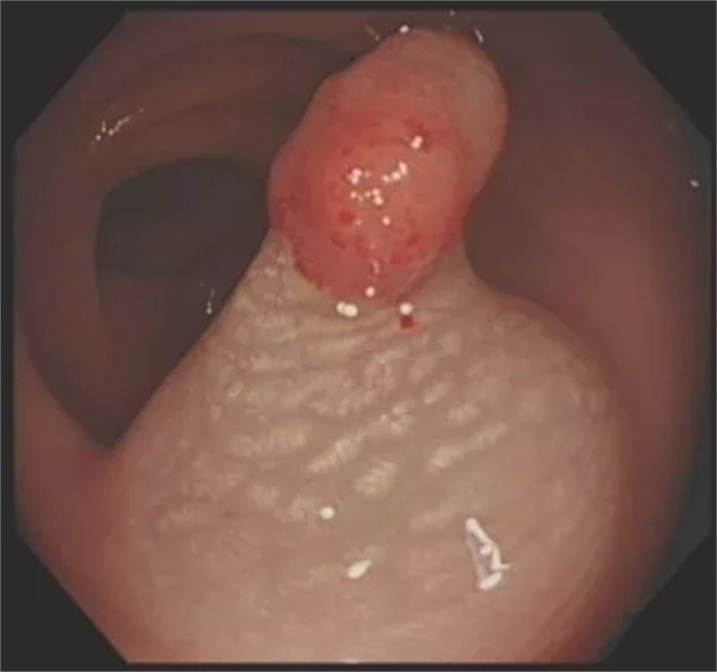

粘膜下注射生理盐水,病灶抬举征明显,周围粘膜可见明显“白斑”。